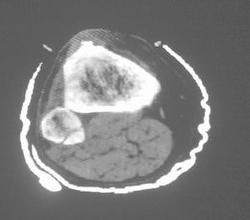

3.CT及MRI檢查

能較好地判斷腫瘤的範圍及侵犯軟組織的情況。MRI可見瘤體處廣泛性骨質破壞,呈軟組織腫塊影;在T1加權像上呈均勻的長T1信號;在T2加權像上呈很長T2高信號。在CT上顯示為源於骨組織的軟組織腫塊,骨質廣泛破壞。